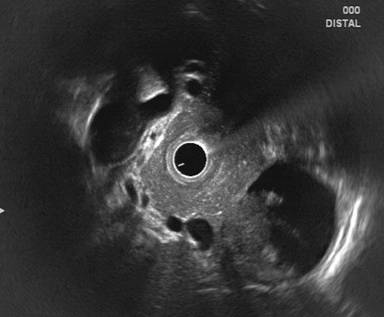

A 19-year-old male presented to us with 3-month history of recurrent upper abdominal pain which aggravated with food intake. He denied any history of vomiting, jaundice and steatorrhea or alcohol intake. There was no history of trauma or any offending drug intake. He had no history of diarrhea, weight loss, or failure to thrive either in childhood or adulthood. There was no family history of pancreatitis or celiac disease. Examination revealed a 6x6 cm soft, epigastric lump. His body mass index was 18.0 kg/m2 (height 1.7 m, weight 52 kg). Investigations revealed a hemoglobin of 11.0 g/dL (reference range: 12.0-18.0 g/dL), total leukocyte count of 4,800 mm-3 (reference range: 4,000-11,000 mm-3) and normal liver and renal function tests. Serum amylase and lipase levels were elevated 3 times above the upper limit of reference. His serum lipid profile, calcium, phosphate and iPTH levels were normal. Ultrasound abdomen and CECT abdomen showed evidence of a cystic lesion (10x8 cm) in relation to body and tail of the pancreas with normal pancreas and no gallstones. Endosonography (EUS) showed evidence of mixed echogenic contents in the cystic lesion (Figure 1), but there were no features of chronic pancreatitis in the form of lobulation, honey combing, calcifications, dilated pancreatic duct or calculi. Tissue diagnosis with fine needle aspiration was not done in view of increased vascularity around the cyst. Since cystic neoplasm could not be excluded, he underwent surgery. At laparotomy the cyst was noted to contain purulent material and hence external drainage was done. Post operatively, his pain abdomen improved and he was discharged.

Figure 1. Radial echoendoscopic image showing the body and tail of the pancreas with normal echotexture and a few hyperechoic foci and strands without calcification or calculi. There is a cystic lesion (10x8 cm) near the pancreatic tail with well-defined walls and mixed echogenic contents. |